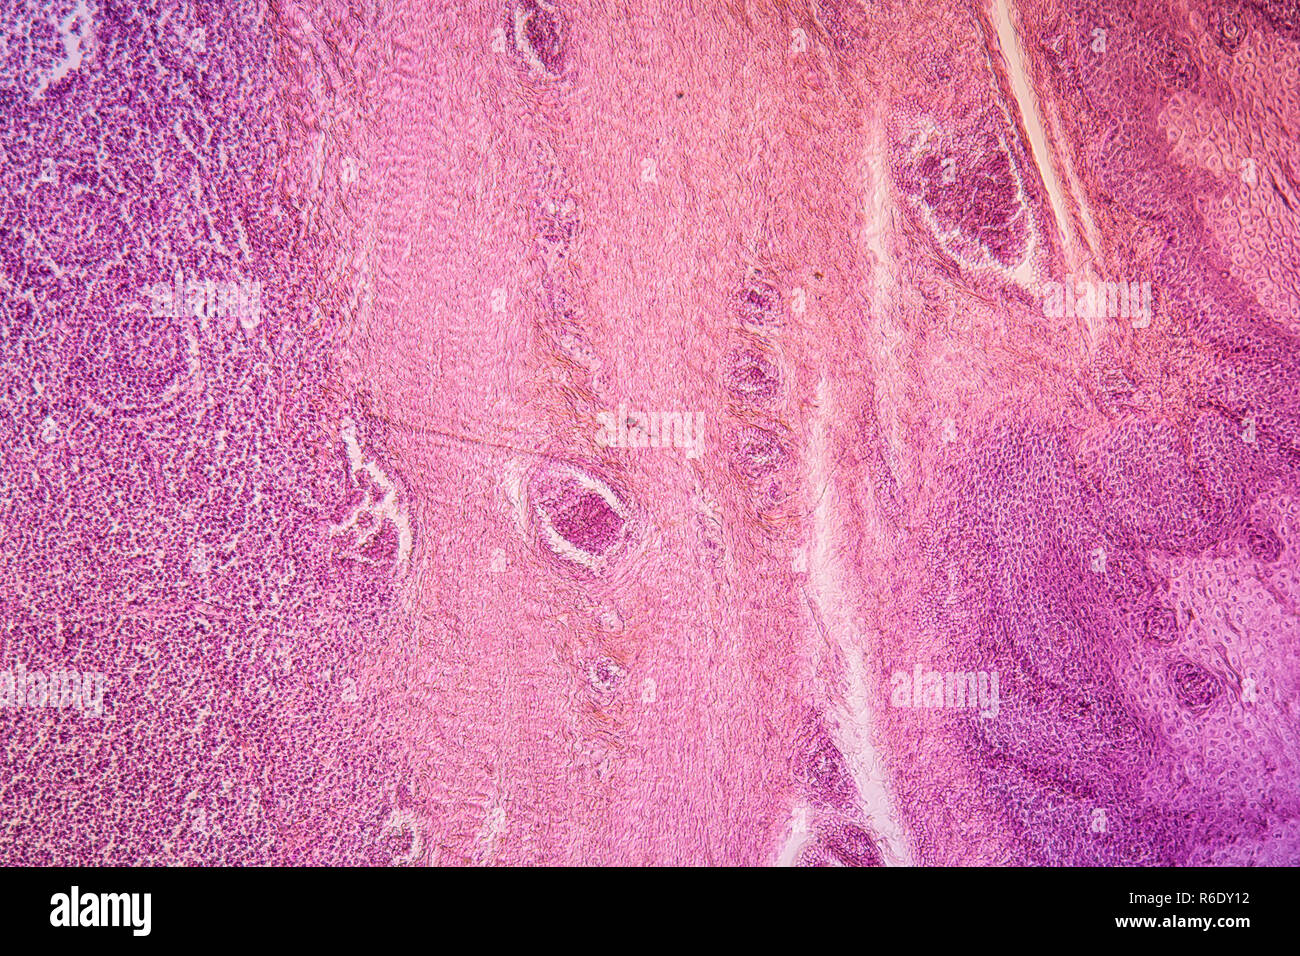

Mandelentzündung krankes Gewebe 100x Stockfotohttps://www.alamy.de/image-license-details/?v=1https://www.alamy.de/mandelentzundung-krankes-gewebe-100x-image227729294.html

Mandelentzündung krankes Gewebe 100x Stockfotohttps://www.alamy.de/image-license-details/?v=1https://www.alamy.de/mandelentzundung-krankes-gewebe-100x-image227729294.htmlRFR6DY12–Mandelentzündung krankes Gewebe 100x